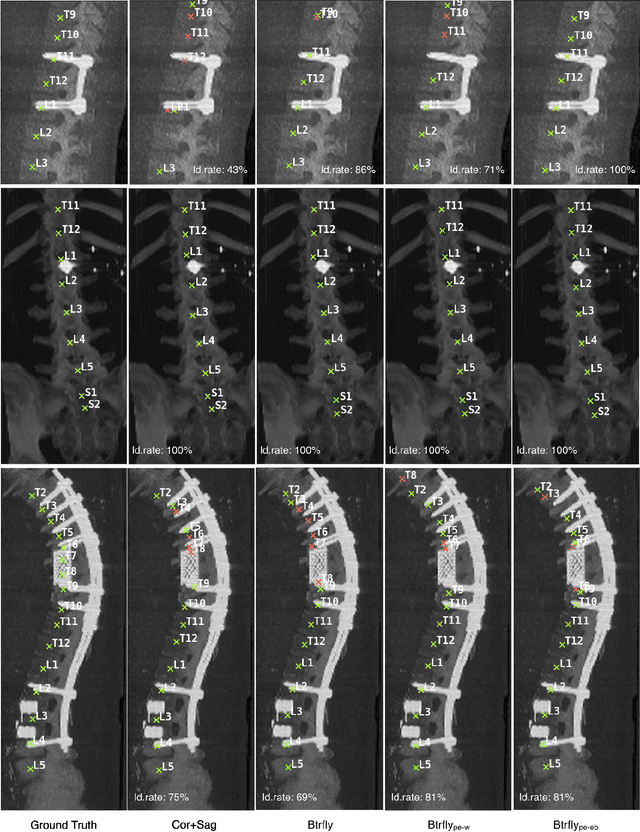

Abstract:Robust localisation and identification of vertebrae, jointly termed vertebrae labelling, in computed tomography (CT) images is an essential component of automated spine analysis. Current approaches for this task mostly work with 3D scans and are comprised of a sequence of multiple networks. Contrarily, our approach relies only on 2D reformations, enabling us to design an end-to-end trainable, standalone network. Our contribution includes: (1) Inspired by the workflow of human experts, a novel butterfly-shaped network architecture (termed Btrfly net) that efficiently combines information across sufficiently-informative sagittal and coronal reformations. (2) Two adversarial training regimes that encode an anatomical prior of the spine's shape into the Btrfly net, each enforcing the prior in a distinct manner. We evaluate our approach on a public benchmarking dataset of 302 CT scans achieving a performance comparable to state-of-art methods (identification rate of $>$88%) without any post-processing stages. Addressing its translation to clinical settings, an in-house dataset of 65 CT scans with a higher data variability is introduced, where we discuss refinements that render our approach robust to such scenarios.

Abstract:Robust localisation and identification of vertebrae is an essential part of automated spine analysis. The contribution of this work to the task is two-fold: (1) Inspired by the human expert, we hypothesise that a sagittal and coronal reformation of the spine contain sufficient information for labelling the vertebrae. Thereby, we propose a butterfly-shaped network architecture (termed Btrfly Net) that efficiently combines the information across the reformations. (2) Underpinning the Btrfly net, we present an energy-based adversarial training regime that encodes the local spine structure as an anatomical prior into the network, thereby enabling it to achieve state-of-art performance in all standard metrics on a benchmark dataset of 302 scans without any post-processing during inference.